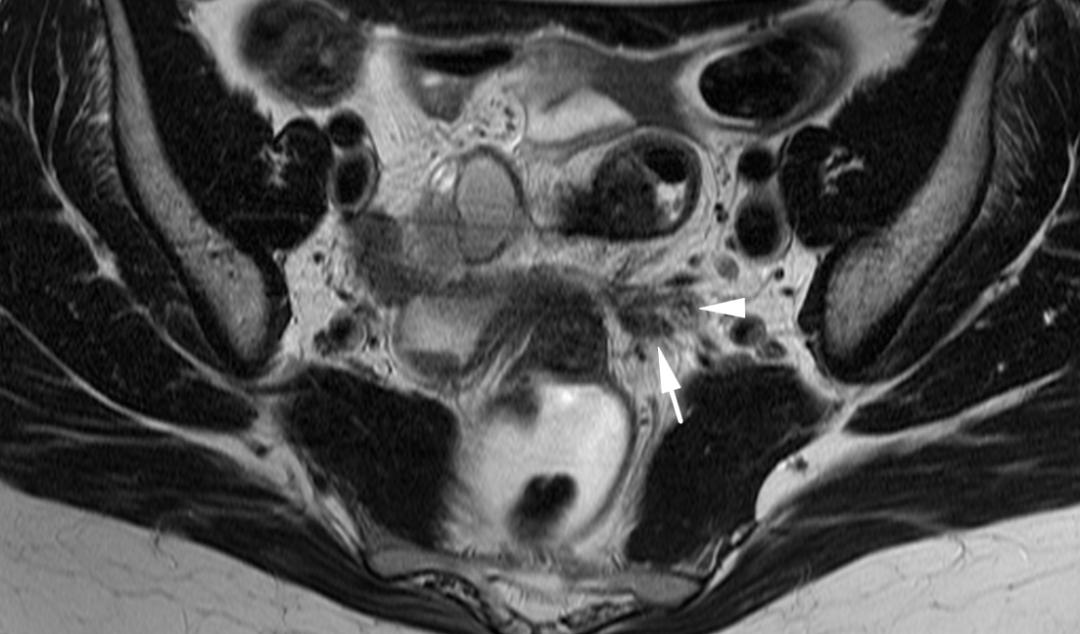

子宫内膜异位至双侧卵巢,T2WI 斜冠位和轴位双侧卵巢类圆形高低混杂信号结节,注意左侧卵巢子宫内膜异位症与乙状结肠之间线性低信号影,提示这些结构之间的粘连。

子宫内膜异位至右侧卵巢,T2WI 轴位发现右侧附件区「葫芦形」高信号,但是更应该注意的是病灶右侧带状低信号,提示与周围结构的黏连。